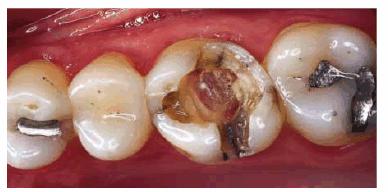

For molars, if there is little remaining tooth structure or the pulp chamber is

shallow, then a post should be used to provide retention for the core (Figur 323s1823d e 18-13A). Usually, only one post is needed.

A prefabricated post should be cemented into the largest canal. In mandibular

molars, this will typically be the distal canal. No attempt should be made to

place a post in the mesial canal of a mandibular molar as the distal wall of

the mesial root is thin and easily perforated. For maxillary molars, a single

post in the lingual canal is adequate. Because the direction of the post is

divergent from the pulp chamber, it creates excellent retention for the core (Figur 323s1823d es 18-13B 18-13C 18-13D 18-13E, and 18-13F

Figur 323s1823d e 18-13A: Prefabricated post with core.

Figur 323s1823d e 18-13B: Tooth #3 after successful root canal treatment.

Figur 323s1823d e 18-13C: Inadequate pulp chamber wall height and lack of remaining tooth structure evident after removal of previous restorative materials. Additional retention with prefabricated post is indicated.

Figur 323s1823d e 18-13D: Completed core build-up on tooth #3.

Figur 323s1823d e 18-13E: Completed crown preparation on tooth #3. Note that the preparation margin extends apical to the core-tooth interface.

Figur 323s1823d e 18-13F: Composite resin may also be used as core material.